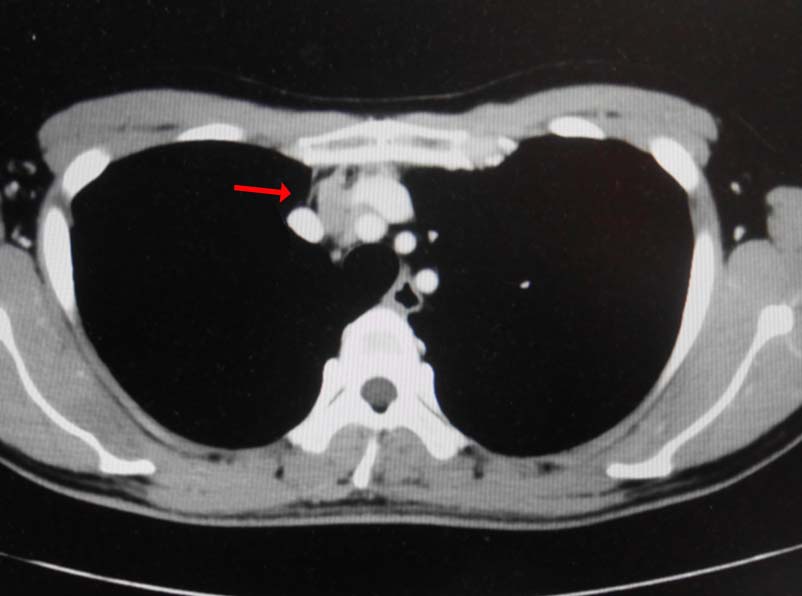

無痛性精巣腫大で泌尿器科受診. 画像診断では, 左精巣最大径4.5cmの腫瘤で縦隔リンパ節転移が疑われた. 左高位精巣摘除術をうける.